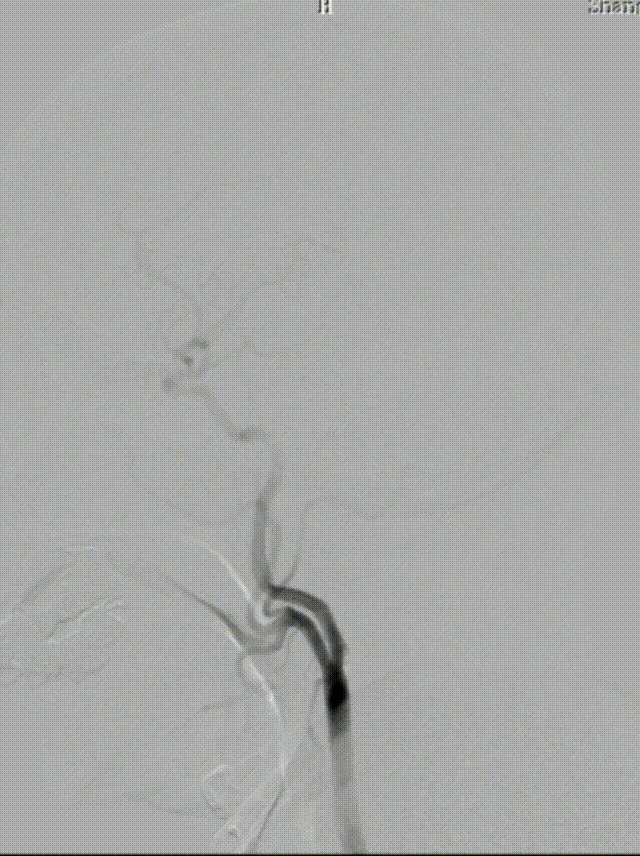

造影见LV闭塞,立即沿0.014*200cm 通桥北斗SS™神经血管导丝置入3mm*16mm 药物球扩支架至LV1。

压力泵逐渐加压球扩支架到8atm, 支架打开良好,造影示残余狭窄0%。

双侧锁骨下动脉造影见椎动脉、基底动脉血流通畅,远端未见栓塞表现。

通桥北斗SS™神经血管导丝操控性优异,术中表现出优良的穿越狭窄病变以及携带支架能力。

左椎支架开口下端斑块完全覆盖,减少远期再脱落风险。